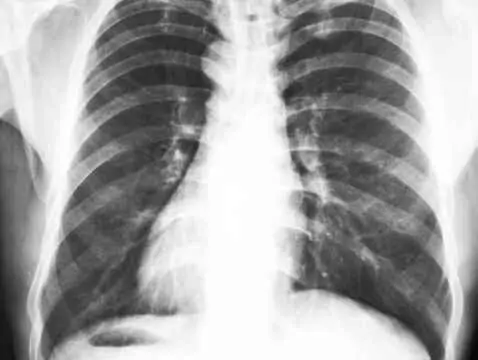

– Wielu pacjentom promieniowanie kojarzy się w następujący sposób: „Stop! Promieniowanie to zło, ja dziękuję!” Niesłusznie – mówi prof. Mirosław Dziuk z Zakładu Medycyny Nuklearnej Wojskowego Instytutu Medycznego, wiceprezes Polskiego Towarzystwa Medycyny Nuklearnej. – Warto wiedzieć, że z promieniowaniem mamy do czynienia na co dzień. Lot samolotem przez Ocean Atlantycki to tak, jak zdjęcie rentgenowskie klatki piersiowej. Nie ma się więc czego obawiać, tym bardziej, że diagnostyka nuklearna jest precyzyjna i dogłębna – pozwala ocenić nie tylko obraz, ale i funkcjonalność danego narządu – tłumaczy prof. M. Dziuk.